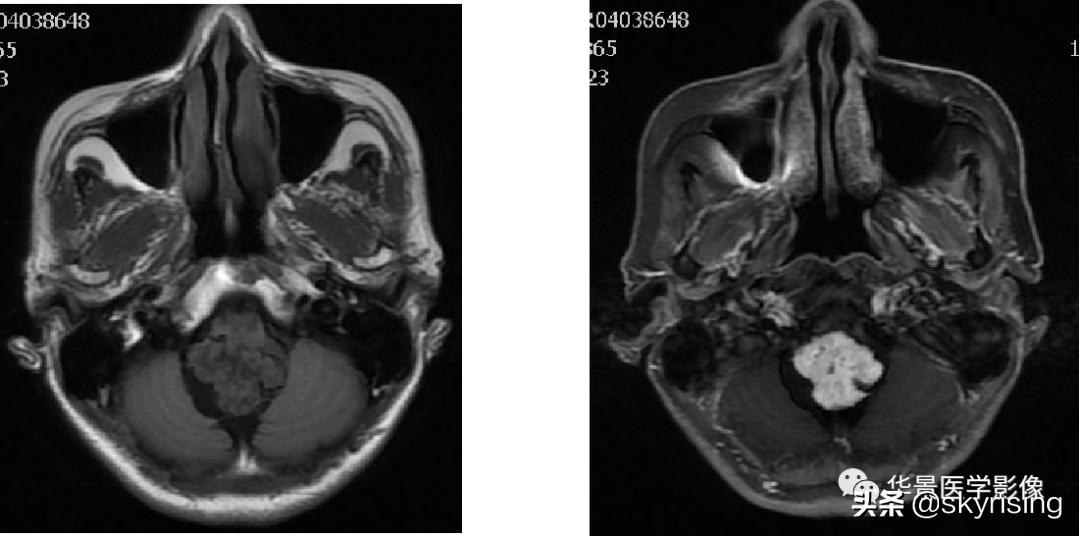

上图白色箭头:小脑延髓池内延髓背侧不规则形团块影,延髓受压变形。

黄色箭头:走行与病灶边缘的流空信号血管影。

上图白色箭头:小脑延髓池内延髓背侧不规则形团块影,小脑半球、延髓、第四脑室受压变形,所见诸脑室未见增宽。

蓝色箭头:延髓受压前后径变窄,T1信号减低,考虑合并水肿。

黄色箭头:病灶边缘见流空信号血管影。